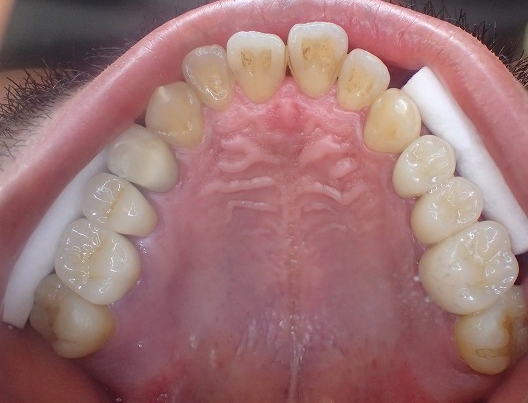

左右5本をジルコニアクラウンにすることができました。

上顎の歯がすべて揃いました。

ご本人は転院前の1本の費用で

5本入ったとお喜びになりましたが

今後の経過が大切です。

来院時には必ず歯肉深くの歯石を除去していますが

もう少し歯磨きを頑張ってください。